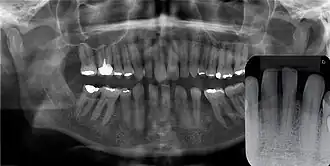

Radiografia panorâmica do CGA mostra agenesia dos incisivos lateriais inferiores e pré-molares. Radiografia panorâmica mostra nenhum envolvimento ósseo.

O cisto gengival tende a não ser visível em radiografias por sua origem ser exclusivamente de tecidos moles, mas em raros casos, seu crescimento pode gerar uma sombra radiolúcida ao causar a erosão óssea, e em alguns casos pode até mesmo se assemelhar ao cisto periodontal lateral pelo aspecto radiolúcido bem delimitado.[2]